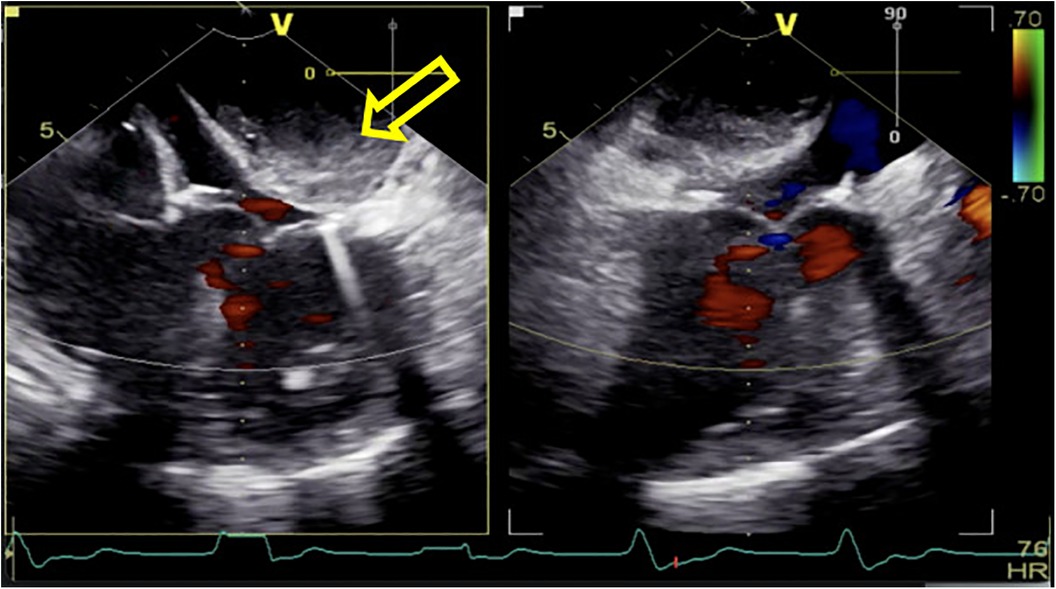

Following routine cardiac general anesthetic procedures, TEE confirmed severe eccentric mitral regurgitation owing to prolapse of the middle scallop of the posterior mitral leaflet along with light tricuspid regurgitation and pulmonary valve regurgitation. The patient's left ventricular ejection fraction (LVEF) was normal (65%). A median sternotomy was performed, followed by standard right atrial and atrial septum access. Mitral valve replacement involved continuous suturing with 2-0 prolene thread, placement of a size 29 bioprosthetic valve, and ligation of the left atrial appendage with double 10-0 sutures. Subsequently, the aortic root was thoroughly deaired under TEE guidance, the aortic clamp was released, and the heart spontaneously started to re-beat. Unexpectedly, during the hemostasis process, the patient's blood pressure gradually decreased, requiring an increase in the dosage of adrenaline and noradrenaline to maintain an appropriate level. At this time, there was no obvious blood loss spots; we also excluded the possible use of medications such as protamine or antibiotics that could have triggered allergic reactions. To determine the cause of hypotension, we conducted an investigation using TEE and discovered a hematoma on the posterior wall of the left atrium, measuring approximately 3 × 4 cm in diameter (Figure 1). This hematoma was rapidly expanding and gradually compressing the mitral valve annulus.

Figure 1

After being weaned from CPB, a rapidly increasing left atrial dissection hematoma (indicated by the yellow arrow) was visible in the posterior atrioventricular groove of the left atrial posterior wall. It gradually compressed the mitral valve annulus, causing relative stenosis of the left ventricular inflow tract.